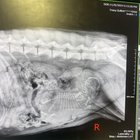

Deși la prima vedere ai putea crede că o sarcină cu un singur pui e mai ușoară pentru mamă, realitatea e exact pe dos. Când o cățea poartă un singur pui, riscurile de complicații la naștere cresc semnificativ. Puiul are mai mult spațiu și, de obicei, crește mai mare decât ar fi normal, ceea ce poate duce la distocie – adică imposibilitatea nașterii naturale din cauza dimensiunii puiului.

• Puiul poate fi prea mare pentru canalul de naștere, necesitând adesea cezariană de urgență.

1. Programează ecografii regulate pentru a monitoriza dezvoltarea puiului și sănătatea mamei.

Cezariana la câini este o intervenție chirurgicală frecventă în cazurile de distocie, mai ales la sarcinile cu un singur pui. Intervenția se face sub anestezie generală și presupune costuri suplimentare, dar salvează viața mamei și a puiului.